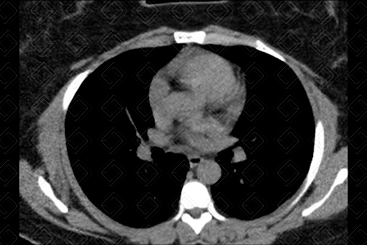

Texto alternativo para a imagem Figura 2. Créditos: Dra. Elazir Mota - Rio de Janeiro/RJ

Descrição das figuras: Tomografia computadorizada do tórax, cortes nos planos axiais, nas janelas de pulmão (onde se visualiza a doença do parênquima pulmonar) e na janela de partes moles (onde se observa o mediastino e suas estruturas, como presença de linfonodomegalias, massas mediastinais, coração e vasos da base).